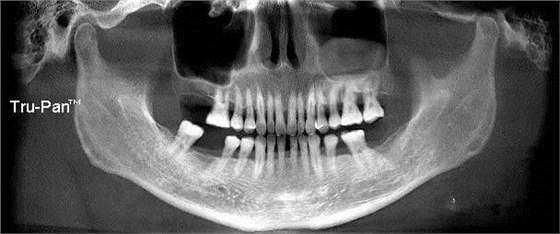

第十圖:上頜竇囊腫,提升區(qū)正好有囊腫,如囊腫小可不處理,直接提升或者抽出囊液減小體積后提升。如果較大,可先將囊腫摘除,三個月后提升(本例采用的就是保留囊腫的外提升已經(jīng)完成兩年)

第十一圖:左側(cè)上頜竇囊腫